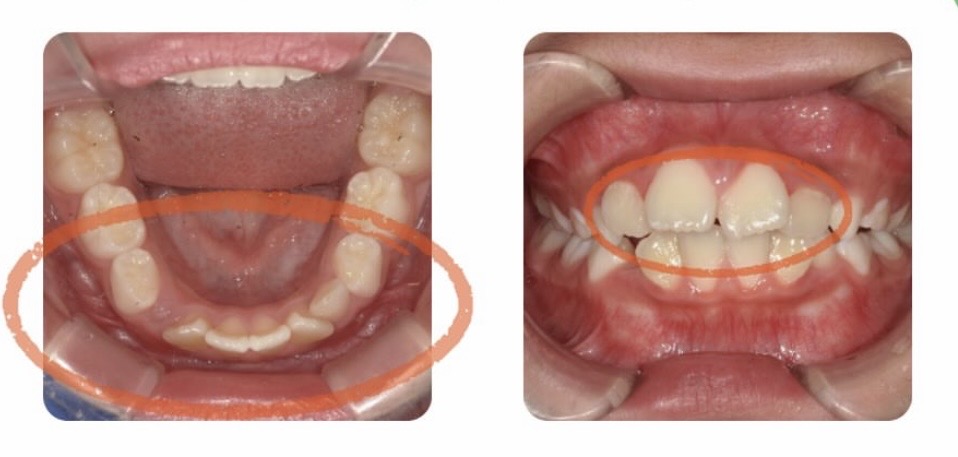

前歯の生え方、下の歯の左右2番目が斜めになっているのが気になり来院されました。

上の前歯が大きく見えるのを本人も気にしていました。

顎が小さく、前歯が前に出ている歯並びをしていると前歯が大きく見える場合があります。

歯の大きさは標準値だったため、現状の歯並びで大きく見えていることを説明し、マイオブレース矯正(myobrace)をスタートしました。